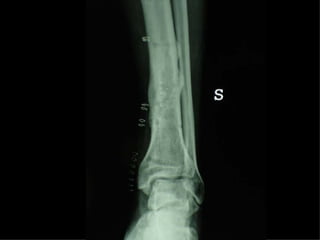

Dal Gennaio 2000 al Febbraio 2006 abbiamo trattato 167 fratture chiuse  con placca percutanea  in 164 pazienti :  27 lesioni diafisarie di gamba, 12 piloni tibiali ,  11 fratture prossimali di tibia, 36 fratture sovracondiloidee di femore, 17 fratture diafisarie di femore, 43 fratture metaepifisarie prossimali di omero, 21 diafisarie d’omero.  156 guarigioni 8 fallimenti

I buoni risultati ottenuti dipendono da 5 punti fondamentali:   una accurata riduzione percutanea della frattura  precise vie di accesso  l’utilizzo della placca che consenta il più lungo braccio di leva possibile il pretensionamento della placca  una sintesi con un ridotto numero di viti

Accurata riduzione percutanea della frattura

Precise vie di accesso

Placche lunghe e pretensionate

Placche lunghe e pretensionate Sintesi con un ridotto numero di viti